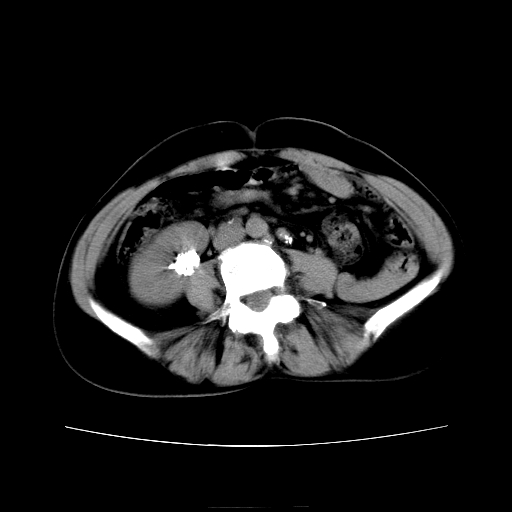

女45y多次(7次)碎石,结果不理想!曾碎石后尿出小碎石,仍腰痛,要求ct,其它不详.本人更倾向于钙化斑!无肾实质破坏,积水等提示集合系统无梗阻.另外腹腔多处钙化.是否结核后改变!谢谢赐教!

1)双肾结石。2)脾脏钙化灶。3)腹膜后多发淋巴结钙化。

尿路结石与腹部淋巴结钙化共存,建议v尿路造影检查,免得钙化灶冤枉为结石受罚。

考虑双肾结石,肾脏实质无破坏表现,没有结核病史,不考虑肾结核,